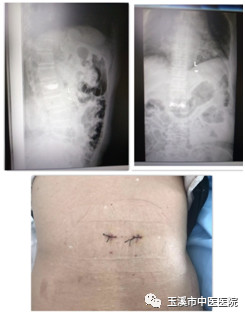

術(shù)中影像資料

術(shù)后影像資料